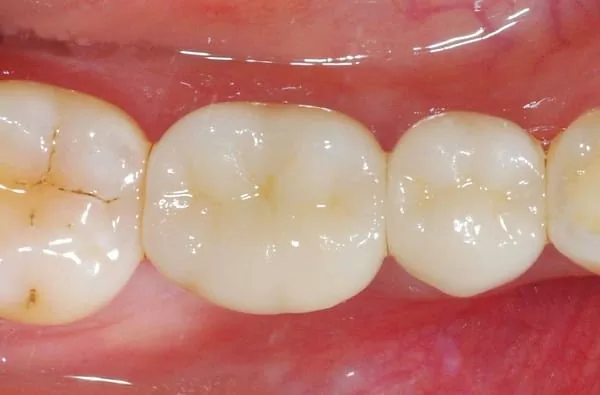

這一天我的新牙齒終於要『入厝』了~~~

醫師將全瓷冠裝裝到我的牙齒裡面,你們看~根本就像是我原來的牙齒一樣嘛~~

上下牙齒對咬的關係好自然喔,既不易塞食物,咀嚼使用起來非常舒適喔!